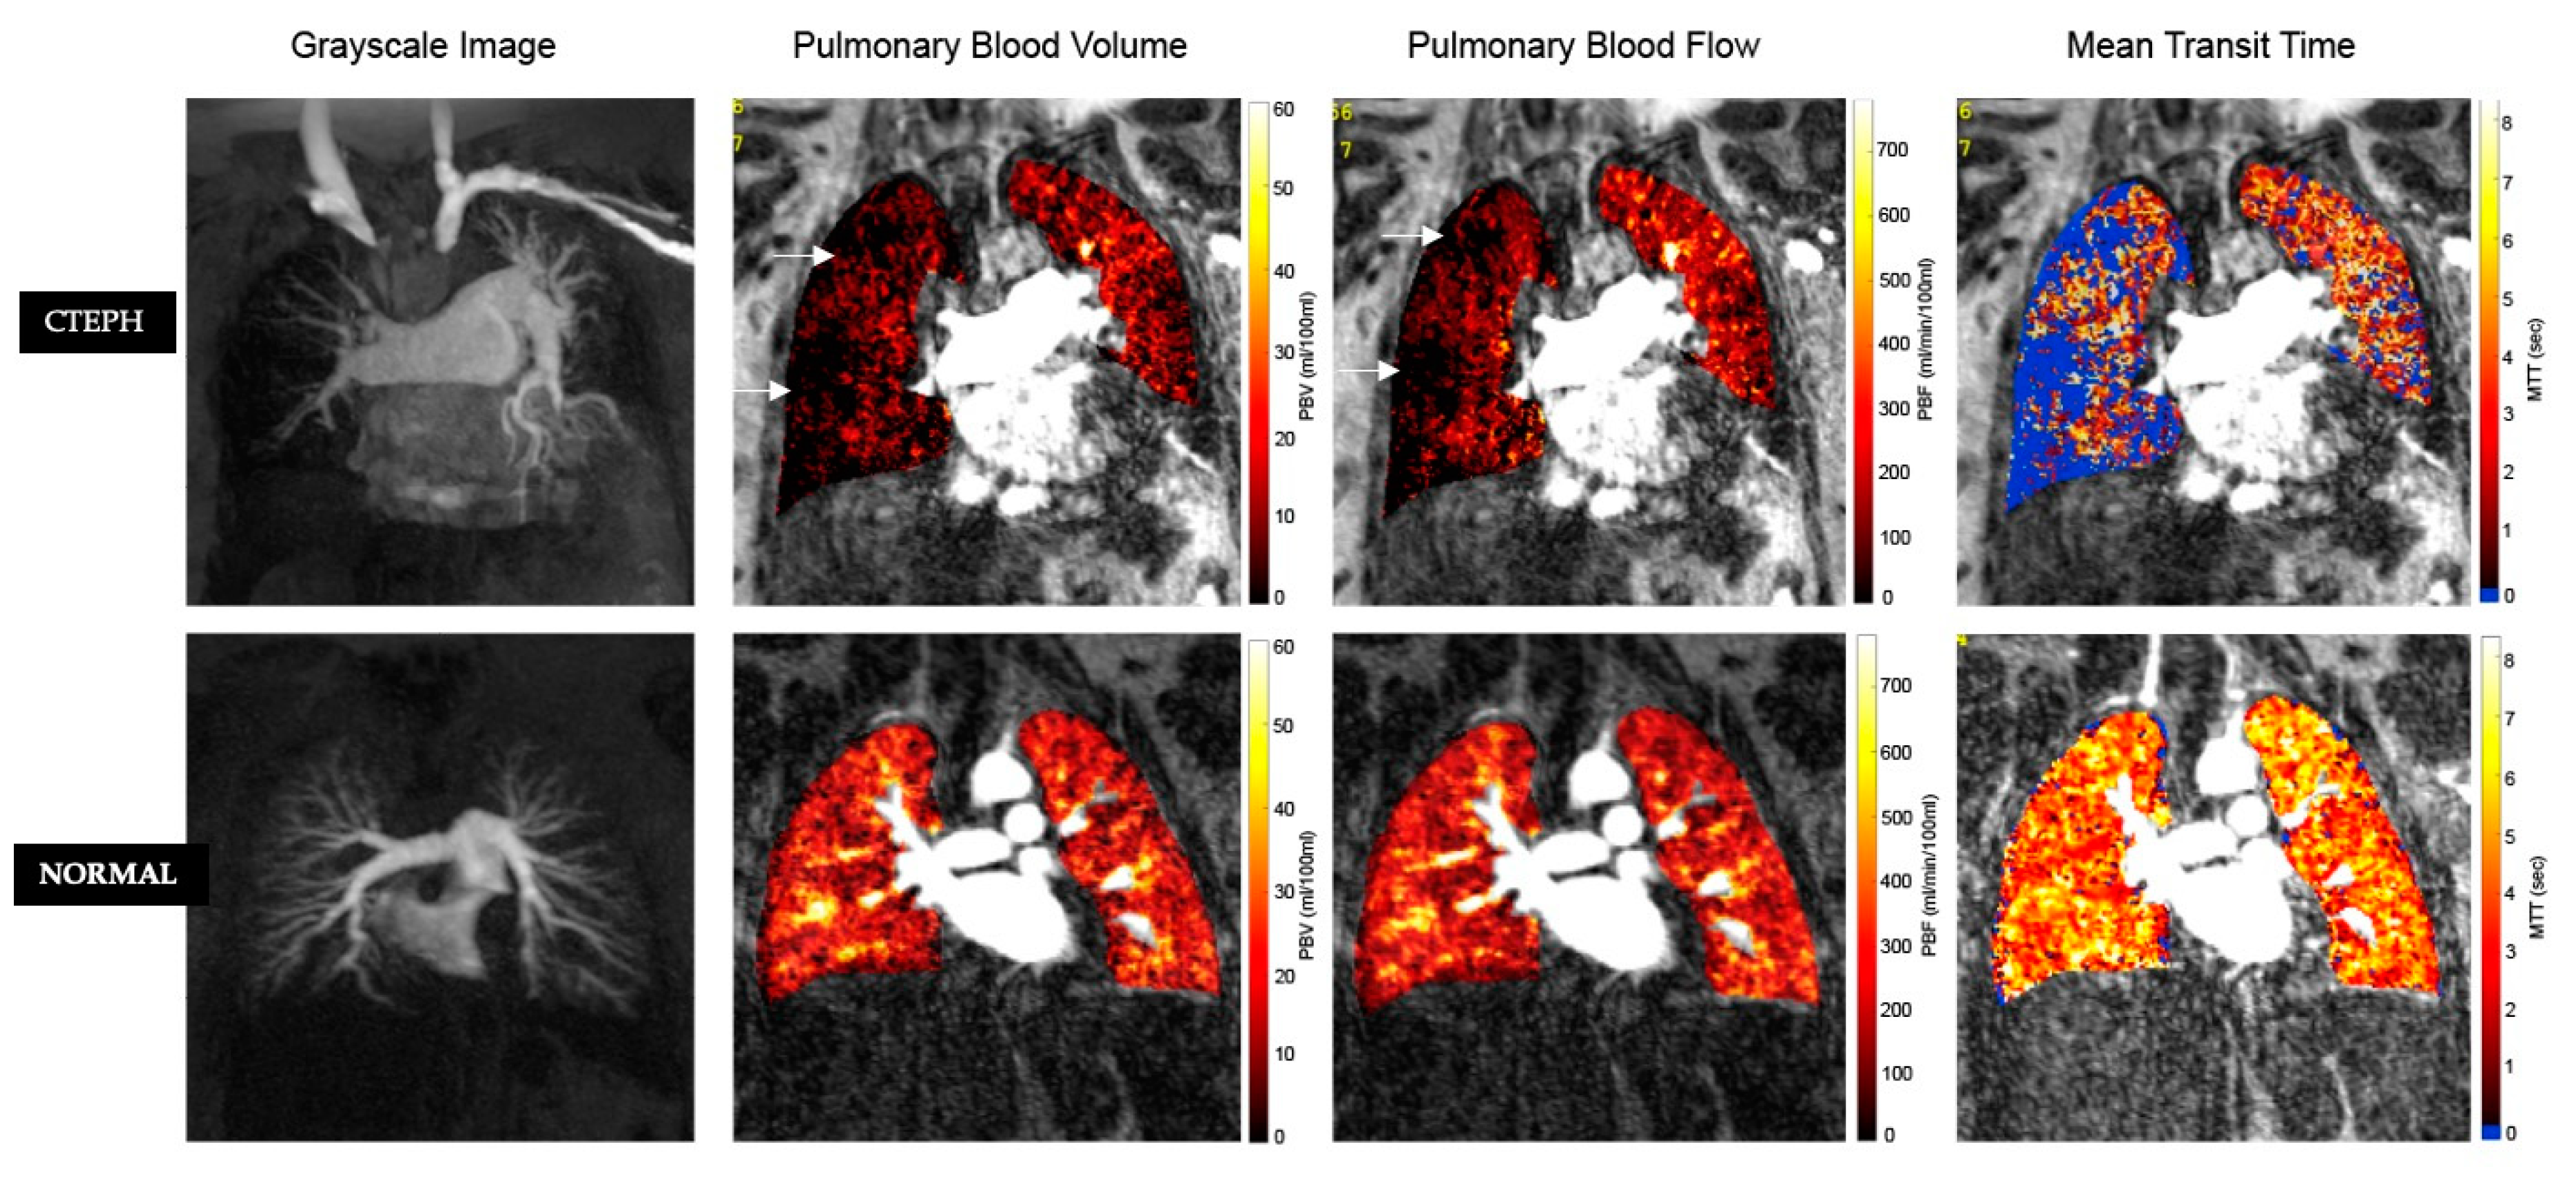

3.3. MR Perfusion